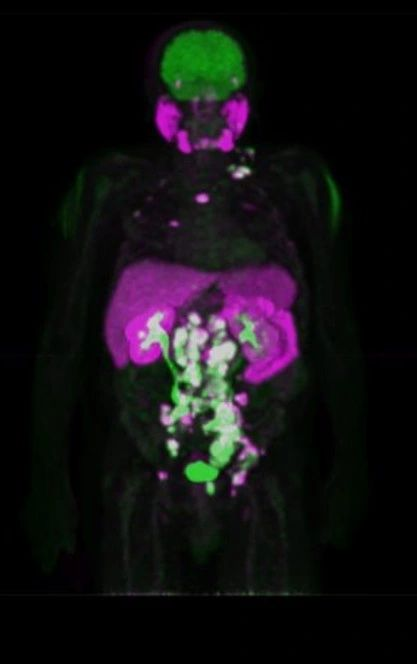

Η Τομογραφία Εκπομπής Ποζιτρονίων (PET) αποτελεί μια εξειδικευμένη μέθοδο της Πυρηνικής Ιατρικής που χρησιμοποιεί μοριακή απεικόνιση για να εντοπίσει και να παρακολουθήσει φυσιολογικές και παθολογικές λειτουργίες του οργανισμού. Συνδυάζοντας τη λειτουργική απεικόνιση της PET με την ανατομική πληροφορία της αξονικής τομογραφίας (CT), η υβριδική εξέταση PET/CT παρέχει εικόνες υψηλής ευκρίνειας και τη δυνατότητα ποσοτικής αξιολόγησης των βιολογικών μηχανισμών σε κυτταρικό επίπεδο.

Η PET/CT αποτελεί εξαιρετικά προηγμένη τεχνική της σύγχρονης ιατρικής απεικόνισης και χρησιμοποιείται τόσο για τη διάγνωση όσο και για την παρακολούθηση της ανταπόκρισης στη θεραπεία.

Οι κυριότερες εφαρμογές της αφορούν την ογκολογία, τη νευρολογία και, σε μικρότερο βαθμό, την καρδιολογία, ενώ συνεχώς αναπτύσσονται νέες χρήσεις σε άλλες ιατρικές ειδικότητες.

Η εξέταση είναι ανώδυνη και ασφαλής, πραγματοποιείται μετά από ενδοφλέβια χορήγηση ραδιοφαρμάκου (συνήθως ¹⁸F-FDG) και καλύπτει συνήθως ολόκληρο το σώμα – από την κορυφή της κεφαλής έως τα πέλματα.